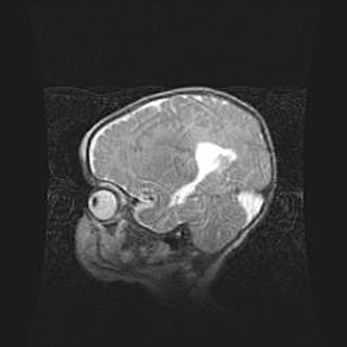

Лейкомаляция с кистозно-глиозной дегенерацией головного мозга.

Возраст: 2 месяца 25 дней

Вес: 6400 г

Окружность головы: 40 см

Срок гестации: 41 неделя

Лейкомаляцию относят к ишемически-гипоксическим повреждениям головного мозга, диагностируемым у новорожденных. При лейкомаляции в головном мозге обнаруживают очаги некроза, возникшие после тяжелой гипоксии и нарушения кровотока. В процессе морфогенеза очаги проходят три стадии: 1) развития некроза, 2) резорбции и 3) формирования глиозного рубца или кисты. Перивентрикулярная лейкомаляция (ПЛ) встречается примерно в 12% случаев среди новорожденных, обычно – у недоношенных детей, причем, частота ее зависит от массы, с которой младенец появился на свет. Наибольшее число малышей страдает лейкомаляцией, если масса при рождении 1500-2500 г.